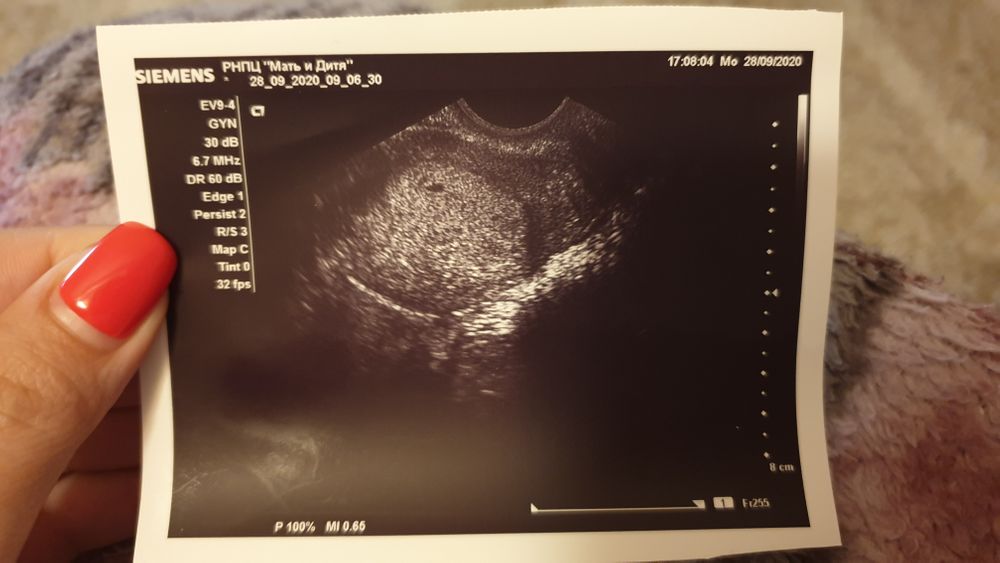

Перед УЗИ меня как-то потрясывало, но оказалось, что зря. Всё на месте🤰 Сегодня 1 неделя задержки, ПЯ 4мм, эндометрий 18. Крепчай, моя крошечка😍